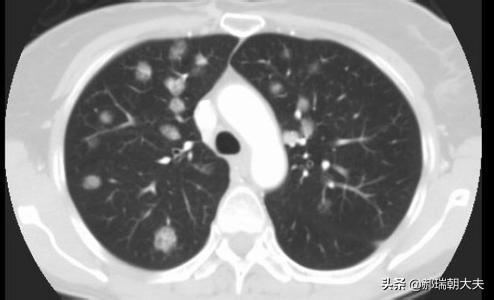

多発性肺結節と孤立性肺結節があり、多発性肺結節は結核やじん肺に続発することが多く、いずれも典型的な病歴や左葉の病歴で診断しやすい。我々が一般的に論じる結節は孤立性肺結節を指す。

健康診断への意識が高まるにつれ、肺結節が発見される人が増えている。肺結節とは画像診断の用語で、肺結節の画像上の定義は、肺実質に完全に囲まれた、境界明瞭な小さな病変(直径≤30mm).結節の形態は、固結または亜固結に分類される。亜固結はさらに、純粋なすりガラス結節と部分的な固結に分類される。直径30mmを超える病変は結節ではなく腫瘤であり、悪性の可能性が高い。

肺結節の約99%は良性病変である。一般的な原因としては、感染性肉芽腫や良性腫瘍(肺悪性腫瘍など)、時には血管や炎症性病変が挙げられる。肺結節の約1%が悪性である。悪性肺結節の一般的な原因としては、原発性肺癌、肺転移およびカルチノイド腫瘍が挙げられる。